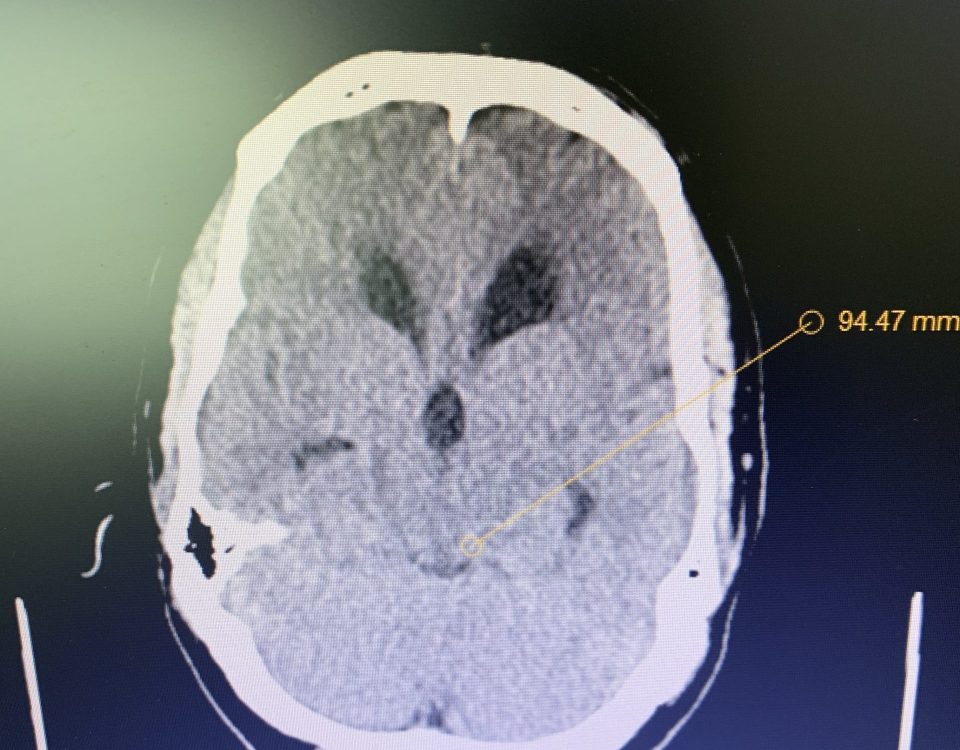

The patient is a 59-year-old gentleman who is otherwise healthy, but states that he had a traumatic head injury several months prior for which he was […]